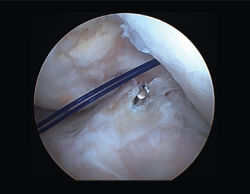

Resolución de problemas al nivel de los túneles

Son varias las situaciones que nos podemos encontrar en lo que se refiere a los túneles:

1. Túneles correctos y en buen estado. Situación ideal en la que, tras una buena limpieza artroscópica minuciosa de los túneles (Figura 20) y la retirada del tejido fibroso, procederemos al recambio simple de la plastia.

2. Túneles en posición no anatómica. En caso de tener suficiente espacio para nuestra plastia, procederemos a su sustitución con nuevos túneles en posición anatómica (Figura 21). Deberemos tener precaución para evitar el colapso del túnel previo. Si hubiera tornillo en dicho túnel y no interfiere con el nuevo túnel, se podría mantener. En caso de no estar ocupado por material, valoraremos el relleno del antiguo túnel (cilindros de injerto óseo, de sustitutivo óseo o, incluso, con un tornillo)(59).

3. Túneles cuasianatómicos, parcialmente ocupados por el material de fijación previo. Podemos realizar varios enfoques, ya que no siempre será necesario retirar los tornillos o sistemas de fijación anteriores, evitando así una pérdida ósea excesiva. Cuando nos encontremos un tornillo de material biorreabsorbible, deberemos proceder a una limpieza exhaustiva del túnel y al cambio en el sistema de fijación (suspensión cortical, por ejemplo). En caso de hallar un tornillo metálico, podemos apoyarnos en este sin necesidad estricta de retirarlo, siempre y cuando nos permita suficiente superficie de contacto óseo para la correcta integración de la plastia. En ambos casos, deberemos aplicar el concepto de “divergencia de túneles” en la creación de los nuevos túneles (Figura 22). Las nuevas guías flexibles y las brocas retrógradas outside-in son de ayuda en estos casos, ya que garantizan un punto de entrada articular deseado, pudiendo modificar posteriormente la dirección del canal óseo para evitar la comunicación de los mismos y una consecuente debilidad en la fijación de nuestro injerto. Debemos evitar el temido efecto de “cañón de escopeta”. De la misma manera, en el caso del túnel tibial, puede ser necesario su relleno con injerto óseo y el cambio de angulación de la guía tibial (medialización/lateralización del mismo).

Algunos autores, sin embargo, se inclinan por el relleno del túnel dilatado con tornillos de gran diámetro o técnica del doble tornillo. También está descrita la “fijación híbrida” con doble sistema de fijación –tornillo más grapa en tibia o tornillo más sistema de suspensión cortical en fémur (Figura 21)–.